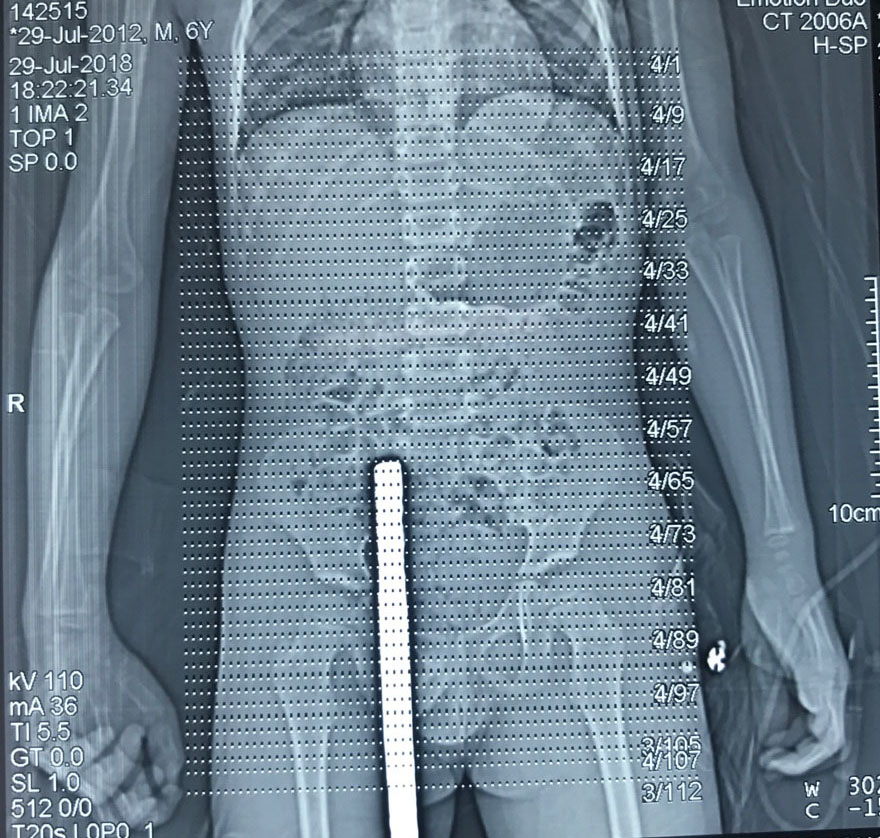

Do nhảy từ tường bao xuống, bé Nh. M , nhà ở huyện An Dương không may bị thanh sắt dài 60 cm đâm xuyên bộ phận sinh dục. Các bác sĩ Bệnh viện Trẻ em Hải Phòng siêu âm, chụp X quang, chụp CT cho thấy ổ bụng không bị tổn thương nghiêm trọng, động mạch chủ và tinh hoàn không bị vỡ hoặc tắc. Các bác sĩ đã tiến hành phẫu thuật và rút thanh sắt ra khỏi cơ thể bé.